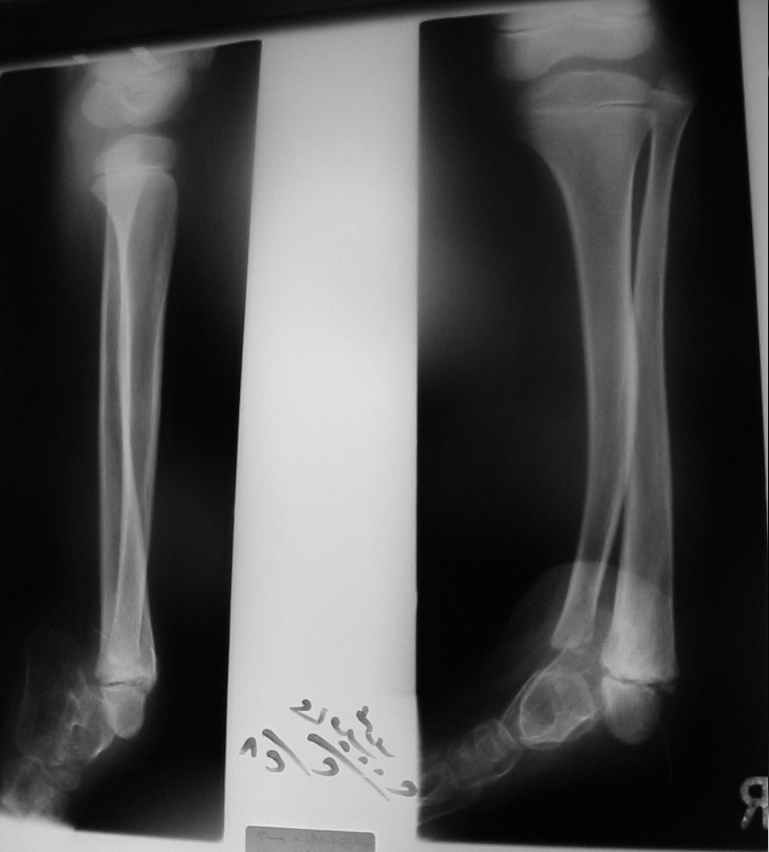

Судя по представленным фото и Рг граммам, у 13 летнего ребенка врождённая гемимелия большеберцовой кости, таранно-пяточный синостоз Из-за отставания в росте большеберцовой кости (остутствует дистальный эпифиз с зоной роста) произошла компенсаторная гиперофия малоберцовой кости, на которую приходится основная нагрузка (спонтанная тибиализация малоберцовой кости). Как результат дисбаланса осевого роста вторично возникла эквино-варусная деформация стопы. Продолжающийся рост ребёнка (до естественного закрытия зон роста) будет приводить к усугублению деформации по приведенным выше причинам.

Своё наблюдение только одно (ребёнка наблюдали и продолжаем наблюдать с рождения) и дважды оперировали: 1 этап выполнили проксимальный тиб/фиб фьюжн вторым этапом медиализация малоберцовой кости с таранно- малоберцовым синостозом и ещё предстоят этапы по удлинению тибиализированной малоберцовой кости.

В вашем случае я бы избрал следующую тактику:

Поднадкостничную остеотомию большеберцовой кости в средней трети с формированием синостоза с малоберцовой ( активно растущей) костью и второй уровень в области дистального тиб/фиб синдесмоза- достигается баланс роста( средне-медиальный и латеральный отделы) в области измененного голеностопного сустава. Коррекция эквино-варусной деформации стопы в аппарате после чрезкожной сегментарной тенотомии ахилова сухожилия. Дело

кропотливое и длительное.

Как резервный вариант может быть рассмотрена ампутация в верхней трети голени с изготовлением функционального протеза, если родители ребенка не настроены на длительную коррекцию и многоэтапную хирургию, родственники должны понимать, что абсолютного функционального результата даже после этапных операций достичь будет невозможно (аномальный голеностопный сустав, таранно-пяточный синостоз).

В принципе согласен с первым вариантом решения проблемы, правда с оговорками. Думаю к двойной остеотомии стоит отнестись с большой осторожностью, ввиду склонности подобных гипоплазированных гостей к ложняку. Если всё-таки решитесь на одноэтапный оперативный метод, то только под прекрытием удовлетворительных результатов сравнительной денситометрии и изотопного исследования.